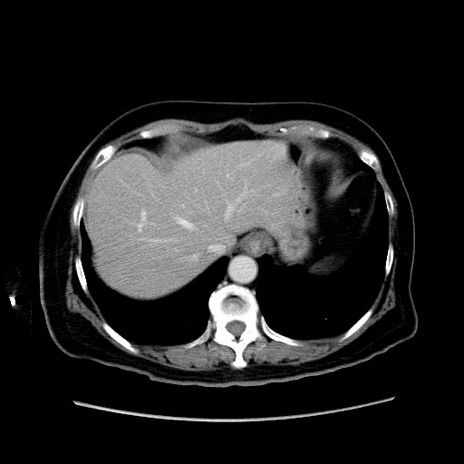

冠状断像

【症例】80歳代女性

【主訴】下腹部痛

【現病歴】約8時間前より下腹部痛の出現あり、救急外来受診。

【既往歴】両側付属器切除

【身体所見】意識清明、下腹部正中に手術痕あり、その部位に一致して圧痛と反跳痛あり。腸蠕動音は亢進。

【データ】WBC 9300、CRP 0.15